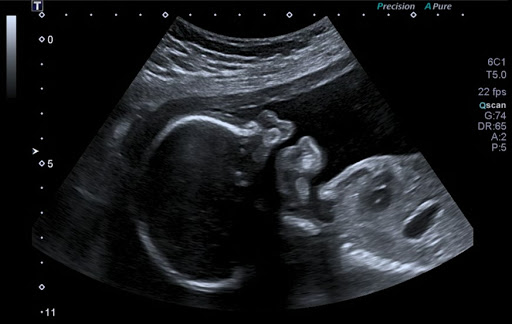

Le pôle d'échographie est un élément essentiel dans le diagnostic et le suivi des pathologies médicales. À notre clinique, nous nous engageons à offrir des soins de haute qualité, en utilisant des équipements de pointe pour garantir le bien-être de nos patients. Nos objectifs incluent la réalisation d'examens précis pour le diagnostic précoce des maladies, le suivi des grossesses et l'évaluation des maladies des organes internes. Nous utilisons des échographes modernes, des technologies d'imagerie avancées et des logiciels d'analyse pour assurer des résultats fiables et détaillés.

La procédure commence par une préparation attentive du patient, où nous expliquons le processus et veillons à son confort. Ensuite, nous réalisons l'échographie dans un environnement calme et rassurant, avant d'analyser les résultats et de les discuter en détail avec le patient. Notre engagement envers nos patients se manifeste par une écoute active de leurs préoccupations, une transparence totale concernant les résultats, une formation continue de notre équipe médicale et un soutien psychologique adapté. En intégrant des technologies avancées et en adoptant une approche centrée sur le patient, nous visons à améliorer la santé de notre communauté et à renforcer la confiance de nos patients envers nos services. v